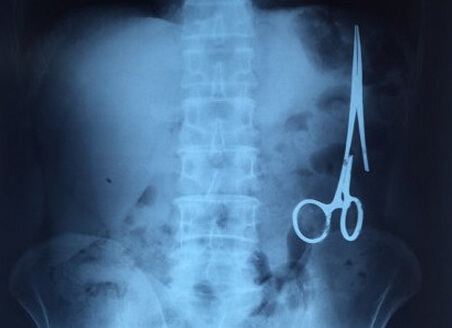

剪刀留腹中18年:X光显示遗留在病人腹中的剪刀

医务人员从X光片中看到,在病人腹部左侧有一把剪刀,与结肠紧挨着。剪刀的把手已经生锈并且有一个把手已经烂断了,患者的部分器官已经与剪刀粘连起来。

ct检查显示,M.V.N的肠子中有一把医用剪刀。M.V.N证实,他曾于1998年6月份在北江省综合医院接受手术,在此后18年来从未进行过任何手术。近来,他感到腹部有些疼痛,并试图通过服用药物治疗。